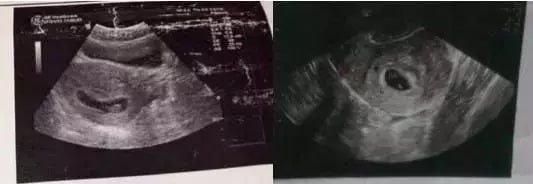

孕囊形状看性别准不准

2022-11-24